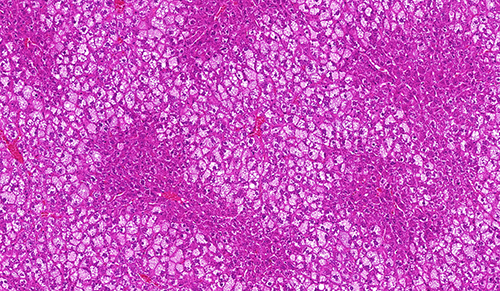

组织检测

实验设计与服务